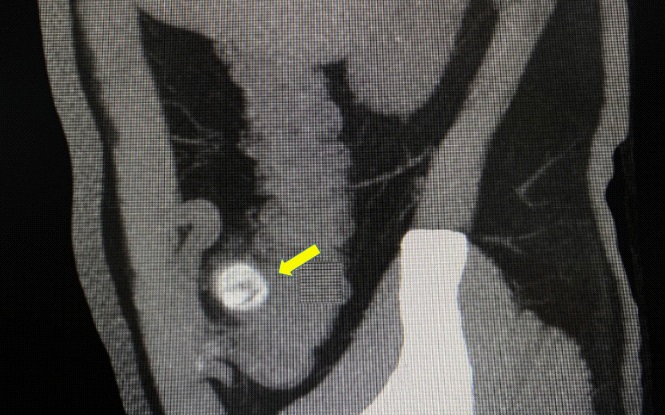

Figure 2: The computed tomography scan of abdomen showed circular high density shadow in right colon, which can be observed in colonic lumen but protruding out of the lumen.

The computed tomography scan of abdomen showed about 20 mm X 20 mm circular high density shadow in right colon, which can be observed in colonic lumen but protruding out of the lumen. Colonoscopy (Figure 3) was also performed and the fecal impaction was identified in the cecal diverticulum above the ileocecal valve. The mucosa surrounding the diverticulum was hyperemic and edema. Than the fecalith was removed successfully with a foreign forceps under colonoscopy. The internal mucosa of the diverticulum was hyperemia, and no perforation was observed (Figure 4). The patient’s abdominal pain were relieved after endoscopic treatment. To prevent recurrence of the disease, surgical removal of the diverticulum was recommended but the patient was hesitant. There was no recurrence of abdominal pain and fecal impaction during 10 months follow-up.